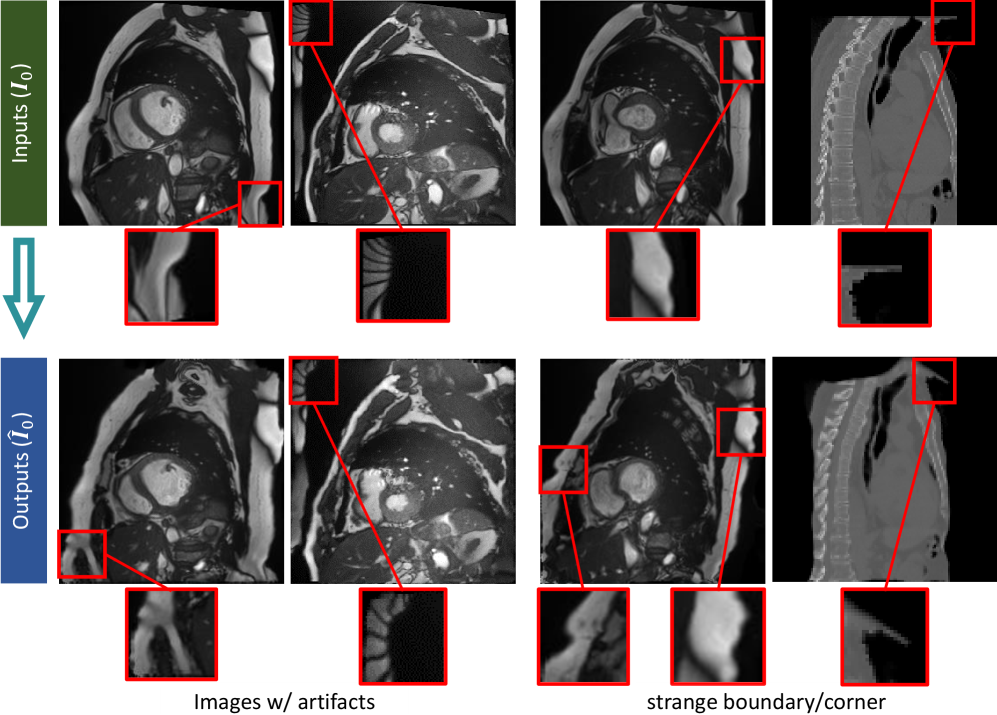

Refer to caption

Figure 13: Artifacts from the original MRI and To occasional cropping of unexpected tissue in CT To images can result in atypical or distorted structures in the To generated outputs (added according to Comment-1.3)

We observed artifacts characterized by sharp corners and irregular boundaries in some generated images (Figure 13). Further investigation identified two primary sources of these anomalies: inherent artifacts present in the original MRI acquisitions, and instances where anatomical boundaries were inadvertently cropped in the original CT data.

Although such imperfections may be undesirable when artifact-free images are required, they can enhance the realism for data augmentation by preserving the noise characteristics of clinical acquisitions. Importantly, the negative Jacobian determinant ratio (Table 1) remains below 1% even for large deformations, confirming that the generated deformation fields are smooth and topologically valid.